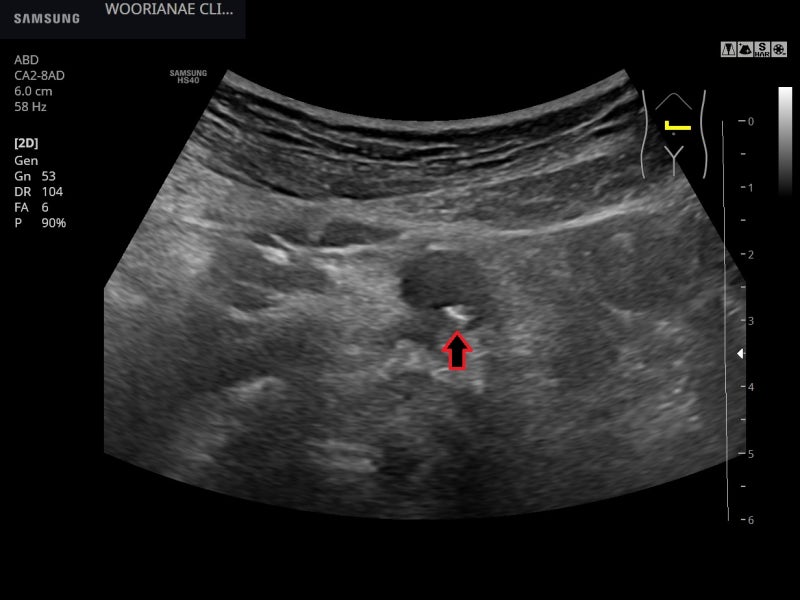

복부초음파 시행 췌장 등 고형 장기는 대부분 잘 관찰됐고 종괴성 병변은 관찰되지 않았다.

대동맥의 비틀림 등을 제거하기 위해 혈관도 관찰하는데… 명확한 동맥경화, 플라크(plaques)가 관찰된다; 20대부터 흡연력

비틀림형 확장 소견(aneurys malchange)은 없었으며 동맥 주변에 저음영 이상 소견은 관찰되지 않았다.

참조 > 저음영으로 보이는 후복강섬유화